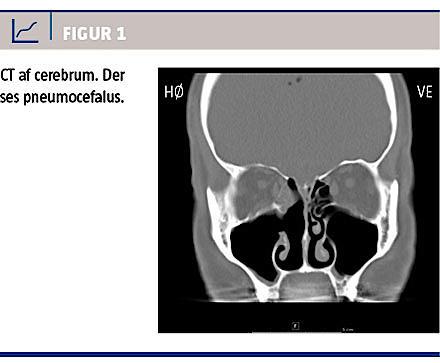

CT af bihuler og cerebrum viste som forventet følger efter resektion af concha media dextra samt partiel resektion af medialvæggen af højre sinus maxillaris. Derudover sås der sløring af højre sinus sphenoidalis og ethmoidalis. Der var pneumocefalus (Figur 1), men knogledefekter kunne ikke påvises. Patienten blev udskrevet i velbefindende efter ti døgns i.v.-antibiotisk behandling.